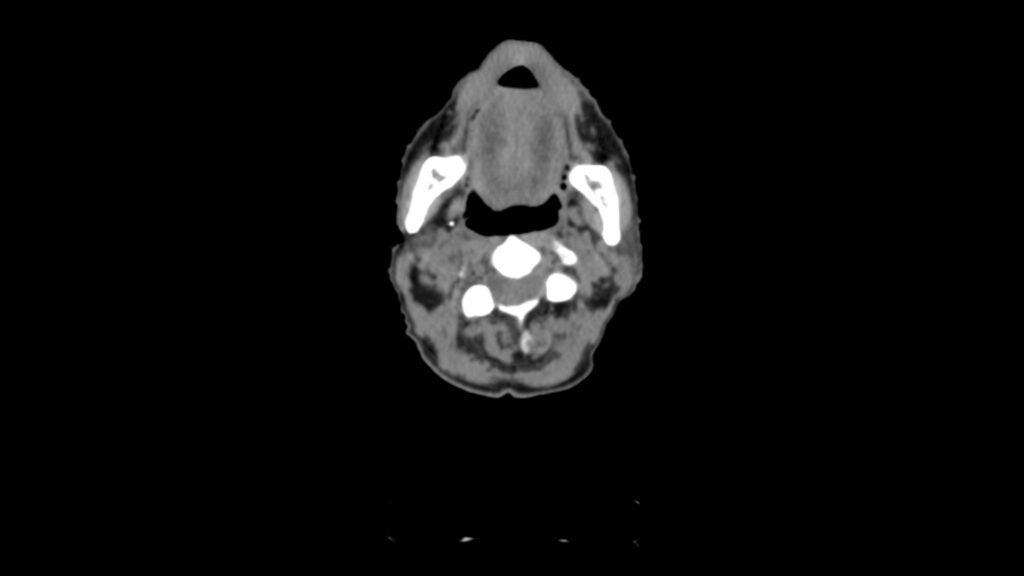

Planning CT Images